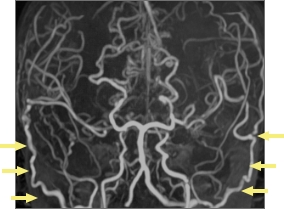

4歳女児症例 脳MRA検査

治療前